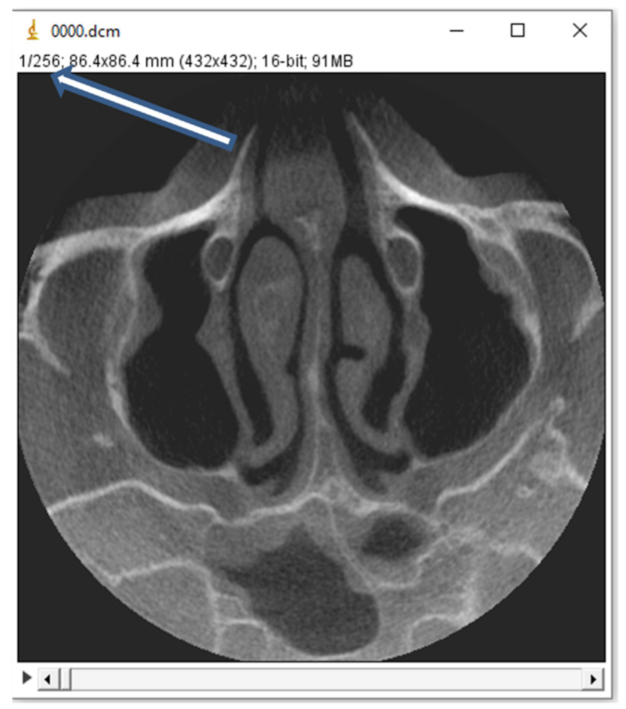

3. Materials and Methods

4. Results